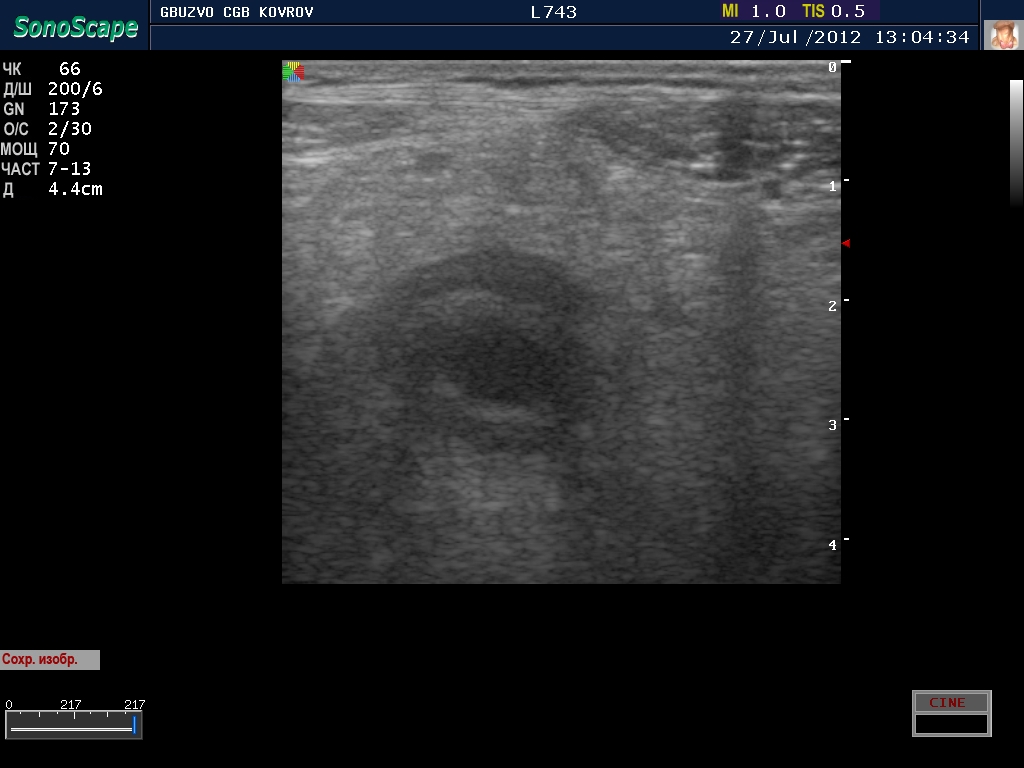

полечили два дня в гастроэнтерологии...состояние ухудшилось, узи контроль----->

поподробнее? :shock: бодимаркер находится в правой подвсздошной области, я бы подумал про аппендикс 8-)